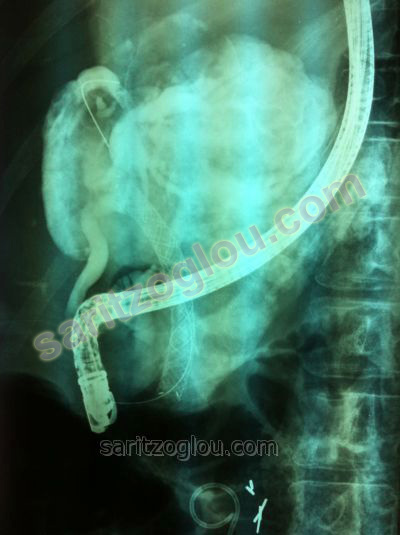

Μεταλλικό stent εξέρχεται του φύματος. Ο ασθενής είχε αποφρακτικό ίκτερο και πυώδη χολαγγειίτιδα λόγω απόφραξης του τελικού άκρου του χοληδόχου πόρου από καρκίνο κεφαλής παγκρέατος. Στην εικόνα φαίνεται να εξέρχεται μεγάλη ποσότητα πύου που είχε συγκεντρωθεί στον χοληδόχο πόρο. (πυώδης χολαγγειίτιδα)